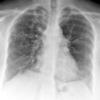

Bronchiectasis

Case 1 PA